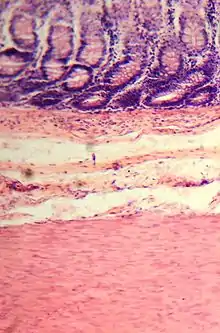

The wall of the large intestine is lined with simple columnar epithelium with invaginations. The invaginations are called the intestinal glands or colonic crypts.

Micrograph of normal large instestinal crypts.

Anatomy of normal large intestinal crypts

The colon crypts are shaped like microscopic thick walled test tubes with a central hole down the length of the tube (the crypt lumen). Four tissue sections are shown here, two cut across the long axes of the crypts and two cut parallel to the long axes. In these images the cells have been stained by immunohistochemistry to show a brown-orange color if the cells produce a mitochondrial protein called cytochrome c oxidase subunit I (CCOI). The nuclei of the cells (located at the outer edges of the cells lining the walls of the crypts) are stained blue-gray with haematoxylin. As seen in panels C and D, crypts are about 75 to about 110 cells long. Baker et al.[30] found that the average crypt circumference is 23 cells. Thus, by the images shown here, there are an average of about 1,725 to 2,530 cells per colonic crypt. Nooteboom et al.[31] measuring the number of cells in a small number of crypts reported a range of 1,500 to 4,900 cells per colonic crypt. Cells are produced at the crypt base and migrate upward along the crypt axis before being shed into the colonic lumen days later.[30] There are 5 to 6 stem cells at the bases of the crypts.[30]

As estimated from the image in panel A, there are about 100 colonic crypts per square millimeter of the colonic epithelium.[32] Since the average length of the human colon is 160.5 cm[12] and the average inner circumference of the colon is 6.2 cm,[32] the inner surface epithelial area of the human colon has an average area of about 995 cm2, which includes 9,950,000 (close to 10 million) crypts.

In the four tissue sections shown here, many of the intestinal glands have cells with a mitochondrial DNA mutation in the CCOI gene and appear mostly white, with their main color being the blue-gray staining of the nuclei. As seen in panel B, a portion of the stem cells of three crypts appear to have a mutation in CCOI, so that 40% to 50% of the cells arising from those stem cells form a white segment in the cross cut area.

Overall, the percent of crypts deficient for CCOI is less than 1% before age 40, but then increases linearly with age.[29] Colonic crypts deficient for CCOI in women reaches, on average, 18% in women and 23% in men by 80–84 years of age.[29]

Crypts of the colon can reproduce by fission, as seen in panel C, where a crypt is fissioning to form two crypts, and in panel B where at least one crypt appears to be fissioning. Most crypts deficient in CCOI are in clusters of crypts (clones of crypts) with two or more CCOI-deficient crypts adjacent to each other (see panel D).[29]